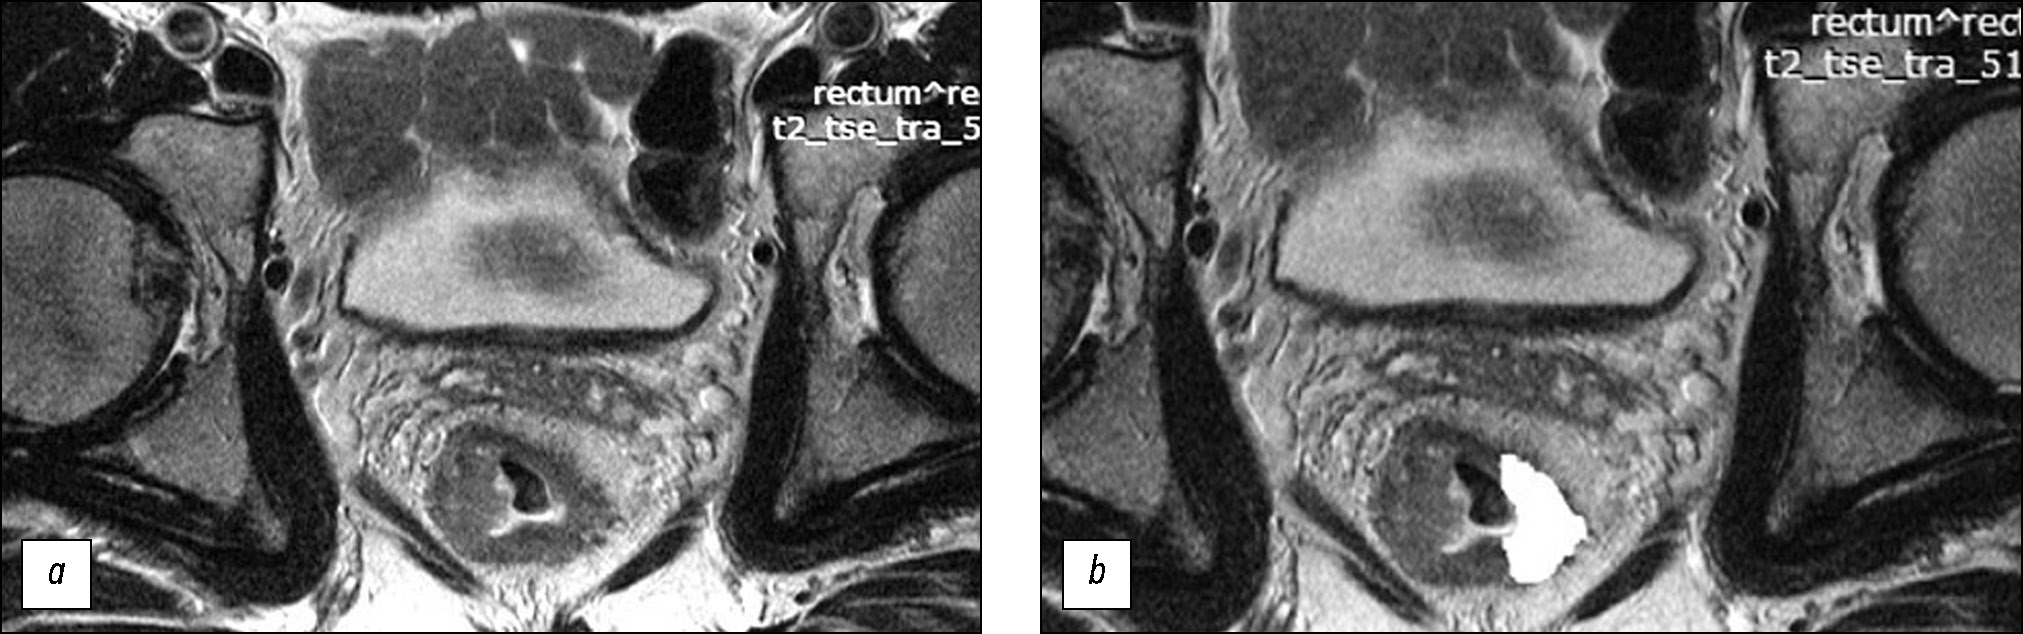

材料和方法。在回顾性研究中接受新辅助放化疗综合治疗的局部晚期直肠癌患者(n=82)被分为训练样本(n=58)和对照样本(n=24)。在肿瘤中心水平使用方向垂直于肠壁的高分辨率原始加权T2图像,用于纹理分析。纹理分析基于灰度级共生矩阵(GLCM),借助MAZDAver计算机程序执行了二阶统计法。 4.6和11个纹理参数的计算。在训练样本中进行手术制剂形态学评估后,查明治疗有反应(预后良好组)和无反应(预后不良组)患者组的纹理分析参数的真实差异,并在此基础上创建评估新辅助放化疗效果的评分系统。系统在对照样本上进行测试确定诊断效率的参数。